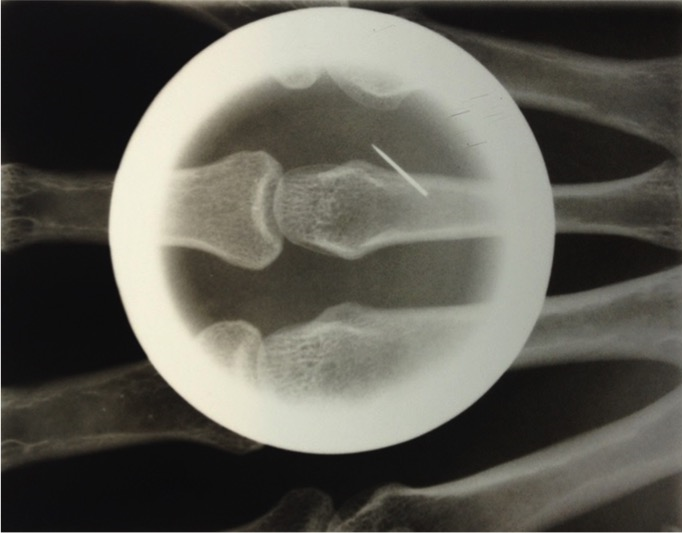

Hand injury from pneumatic needle gun

A 37-year-old male complained of pain and swelling of his left hand for 7 days. He was a woodworker and reported that he was using a pneumatic needle gun when the pain began. The patient claimed to have seen a scorpion in the workplace and he believed to have suffered a sting. Initially he sought an emergency room, where hydrocortisone and ketoprofen were administered, and loratadine was prescribed. Because it does not show improvement with seven days of loratadine, he sought the dermatology service. On physical examination, heat, redness and swelling of whole left hand was observed. Dermoscopy with a handheld dermoscope (DermLite II Pro 3Gen) showed a single puncture wound over volar surface of the third left metacarpal. Hand X-ray revealed a foreign body in soft tissue of third left metacarpal. The diagnosis of hand injury from pneumatic needle gun was made. Foreign body was identified and removed. Intravenous antibiotics were administered pre-operatively and oral antibiotics continued post-operatively. Nail gun injuries commonly occur related to improper use by the operator and not following occupational health and safety requirements for operating a nail gun. The amount of energy required to cause serious injury is fairly low: penetration of the skin occurs with projectile velocities of 150 feet per second, whereas bony fractures may occur with projectile velocities of 195 feet per second. Mechanisms of nail gun injury include direct penetration, shrapnel wounds from exploding cartridges and high-pressure injection injuries from the compressed air used to activate the gun. Assessment of a patient with a puncture wound and suspected foreign body begins with a careful history and physical examination.